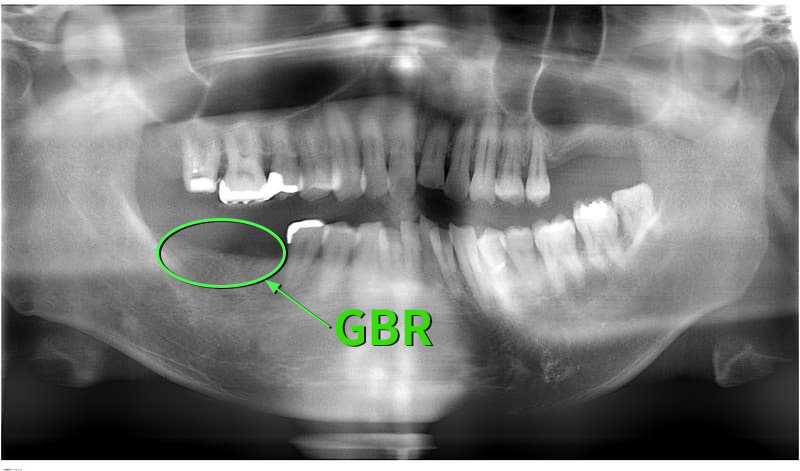

病歴や健康状態に関する問診、口の中の検査、レントゲン写真や歯型の採取

- 外科処置によって顎の骨にインプラントを埋め込みます。